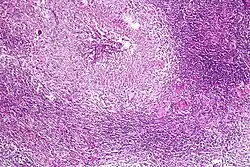

Pulmonary tuberculosis featuring necrotizing granulomas, H&E stain.

Pulmonary tuberculosis featuring necrotizing granulomas, H&E stain. -